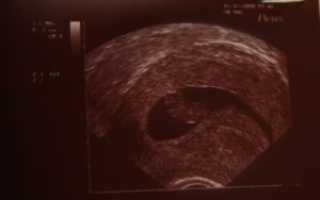

Беременность 6 недель может стать поводом для УЗИ, только если врач предполагает, что она многоплодная, либо у женщины были в анамнезе выкидыши и случаи внематочной беременности. В обычной ситуации в проведении ультразвукового обследования сейчас нет необходимости.

УЗИ обычно проводят трансвагинальным датчиком – на этом сроке данный способ более информативен. Будущая мама сможет услышать, как бьется сердечко ее малыша, увидеть его на экране монитора и на фото.

Врач делает выводы о расположении плодного яйца, его размерах и точном сроке беременности.

При обследовании может быть назначено УЗИ на 6 неделе беременности. На таком сроке УЗИ позволяет определить наличие плода в матке, то есть, исключить внематочную беременность. Можно увидеть, сколько плодных мешочков начали свое развитие в матке, то есть, выявит многоплодную беременность.

На таком сроке плод мало напоминает ребенка, эмбрион выглядит, как зернышко фасоли, да и его размер напоминает зернышко. Но зато при проведении УЗИ можно будет увидеть сердцебиение плода.

Фото плода на 6 неделе беременности

УЗИ на шестой неделе беременности помогает оценить наличие развивающейся беременности, врач использует трансвагинальный датчик из-за того, что он дает более четкие данные.

При ультразвуковом обследовании увеличивается размер матки, уже различаются отдельные части тела и органы плода. Можно прослушать сердцебиение малыша. На УЗИ до сих пор виден желточный мешок и желтое тело в яичнике.